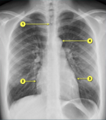

1. A 37-year-old man, with no known medical illness, came for a routine medical check-up. His chest radiograph is presented to you. Identify the incorrect statement with respect to the X-ray shown below.

1. The structure marked as number 2 is right ventricular border

2. The structure marked as 1 is the trachea

3. The structure marked as 3 is the left ventricular border

4. The structure marked as 4 is the aortic arch